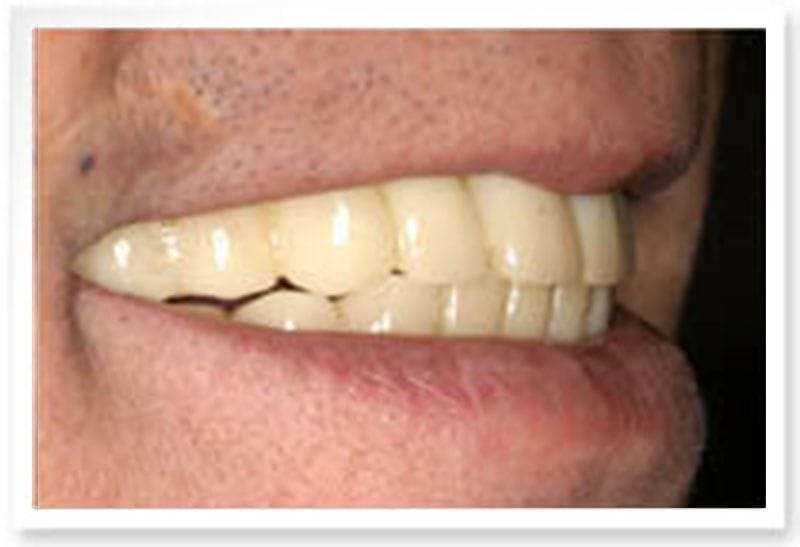

治療後

治療後-口外側面